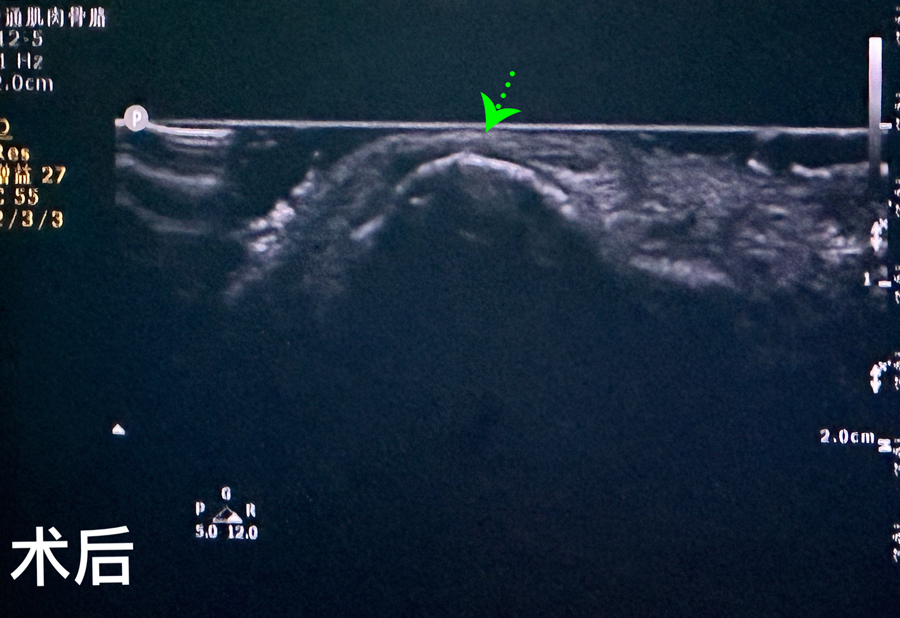

8月15日,彬彬家长在辗转多家医院后,听说a片网站 有鼻骨骨折复位新技术,立即带彬彬赶到医院。此时,距离彬彬鼻骨骨折已经过去一周了。就诊时,彬彬鼻部肿胀已经消退了,能看到他的鼻梁是向左侧偏曲的,妈妈特别希望孩子的鼻梁能恢复到从前高挺、居中的状态。国家儿童医学中心、北京儿童医院耳鼻喉头颈外科常驻专家、a片网站 副院长张薇,a片网站 耳鼻喉科主任李莉萍为其进行鼻部检查,并结合鼻骨CT全面评估后,决定采用超声引导下鼻骨骨折复位术,以实现精准复位,使彬彬的面容不受影响。8月16日,张薇副院长、李莉萍主任及手术室、麻醉科医护人员组成手术团队,为彬彬进行手术。术中,医生在超声引导下应用复位器对游离骨片进行复位调节,使错位的鼻骨重新连续。10分钟后,手术顺利完成,复位后的鼻子外观无畸形。术后,彬彬接受抗感染治疗48小时,情况稳定,顺利出院。

相比较传统凭经验及手感的鼻骨复位术,超声引导下的手术复位能更精准定位到损伤部位,如医生的“透视眼”,实现手术可视化,使医生在术中可准确看到鼻骨断端的对合情况,在“精准、微创、美观”上得到极大优化和提升。患儿无伤口、恢复快。术前和术后鼻骨错位及对合情况B超均有图片准确显示,让家长也能看明白,患儿和家长的心理负担明显减轻不少,改善了就医体验。